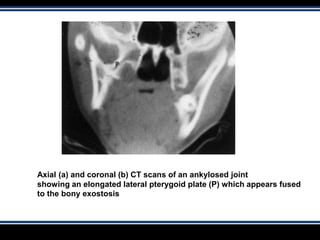

Axial (a) and coronal (b) CT scans of an ankylosed joint

showing an elongated lateral pterygoid plate (P) which appears fused

to the bony exostosis